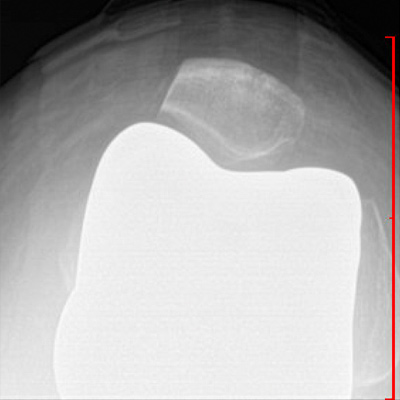

Lateral View Total Knee Replacement